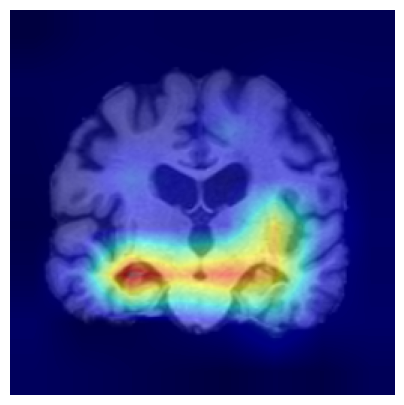

4.3.2 ADNI

We consider two groups constructed from the ADNI dataset based on hippocampal volume, a well-established neuroimaging biomarker of Alzheimer’s disease–related neurodegeneration. Each group includes 918 2D slices. Subjects exhibiting reduced hippocampal volume indicative of hippocampal atrophy are assigned to Group 1, while subjects with preserved hippocampal volume form Group 2. This stratification induces group differences associated with disease-relevant anatomical variation and provides a clinically meaningful setting for evaluating whether the proposed feature-level explanations highlight brain regions known to be implicated in Alzheimer’s disease/cognitive impairment.

We use a ResNet-50 encoder pretrained on the UK Biobank dataset, predicting the age of brains, and adapt this pretrained model using a linear probing strategy on the ADNI dataset. Specifically, we train a logistic regression layer on top of the frozen encoder to predict group membership, while keeping all encoder parameters fixed. After training, the linear head is discarded, and the frozen encoder is used to extract embeddings for two-sample testing and for generating feature-level explanations. We apply the proposed feature-level explanation method to individual MRI scans and assess whether the resulting attributions align with known disease-related neuroanatomical patterns.

To assess the robustness of our feature-level explanations, we apply multiple channel-aggregation strategies to the gradients of the test statistic: (i) gradient-weighted aggregation Selvaraju et al. (2017), (ii) second-order gradient aggregation Chattopadhay et al. (2018), and (iii) layer-wise spatial aggregation Jiang et al. (2021). Across all variants, the resulting heatmaps remain consistent. Additional details are provided in the Supplementary Material.

Results.

Figure 7 indicates the qualitative results. Our explainability method consistently highlights the hippocampal and medial temporal lobe regions, and the resulting heatmaps show strong correspondence with areas affected by hippocampal atrophy. These results supports that the identified regions align with established AD biomarkers.